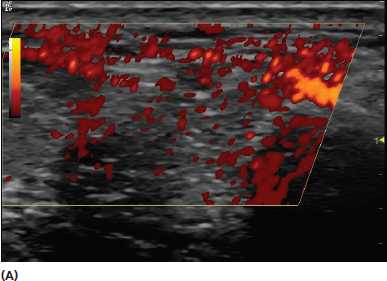

Артефакт "вспышки" - флеш-эффект - всплеск цветового сигнала, заполняющий всю рамку, вызванный движением внесосудистых структур (например, перистальтика кишечника, движение воздуха в трахее).

- движение внесосудистых структур

- быстрое движение датчика.

- изменение фильтров

- адекватная скорость перемещения датчика.